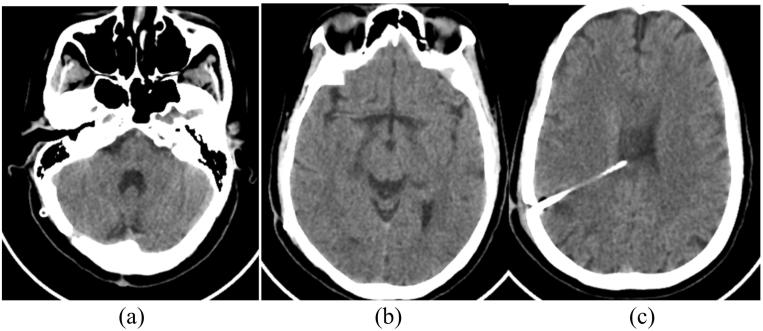

A 54 years old obese woman with previous history of total abdominal hysterectomy was reported. She underwent repeated (three times) revisions of failed peritoneal end of her VP shunt on a background of obstructive hydrocephalus secondary to a posterior fossa tumour (previously excised). Following repeated failure of peritoneal catheter function, she underwent VA shunt and did well.

The decision to place a VA shunt was made after careful deliberations. We discuss the peculiarities in placing a VA shunt. Following placement of a VA shunt, improvement was noted in her clinical condition at one week post op and has been sustained at multiple follow up clinic visits.

报告了一名54岁肥胖女性,既往有全腹子宫切除术史。她因后颅窝肿瘤(先前已切除)继发梗阻性脑积水,在VP分流术失败后,对腹腔端进行了反复(三次)修复。在腹腔导管功能反复失败后,她接受了VA分流术,术后情况良好。

在仔细权衡后决定进行VA分流术。我们讨论了放置VA分流术的特殊之处。放置VA分流术后,术后一周她的临床状况有所改善,并在多次随访门诊中持续保持。